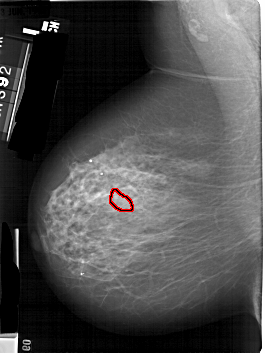

A_1824_1.LEFT_MLO

FILE: A_1824_1.LEFT_MLO.OVERLAY

TOTAL_ABNORMALITIES 1

ABNORMALITY 1

LESION_TYPE CALCIFICATION TYPE PLEOMORPHIC DISTRIBUTION SEGMENTAL

ASSESSMENT 4

SUBTLETY 3

PATHOLOGY MALIGNANT

TOTAL_OUTLINES 1

BOUNDARY